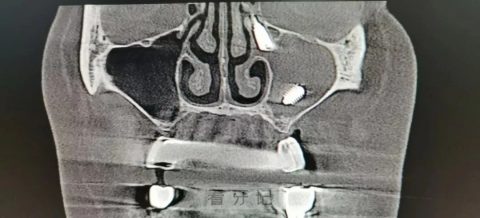

影像可清晰看到鼻腔内的异物

一般来说,种植牙的移位多在上颌窦的窦底,而张女士是在上颌窦的窦顶。窦底是在牙床上方,窦顶是在眼眶下面,这之间的距离约3.75厘米,每块骨头都很精密复杂,加上鼻窦又四通八达,神经、血管密布,手术难度特别大。给张女士手术时,能看到她的上颌窦里的粘膜已经出现增生,一碰就出血,增加了寻找异物的难度。